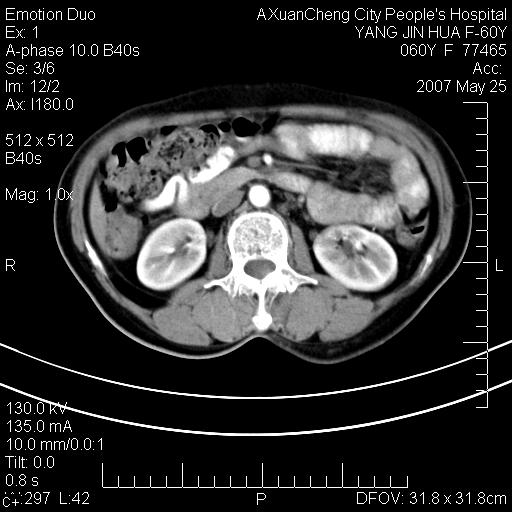

这个病理增强扫描之前,我们是考虑是血管瘤,可是现在增强后一点强化都没有,还能考虑是血管瘤吗

其内可见斑点状静脉石,血管瘤有时就不增强化,还是血管瘤。

1、病灶内有小点状钙化,静脉石?这可是血管瘤诊断的重要征象

2、病灶内有脂肪组织增生,血管瘤有此特点

还是考虑皮下血管瘤,强化不明显可能跟大量血栓形成有关,好多战友考虑血管平滑肌脂肪瘤,血管平滑肌脂肪瘤的血管就不强化么?只要有血管就都应该强化。